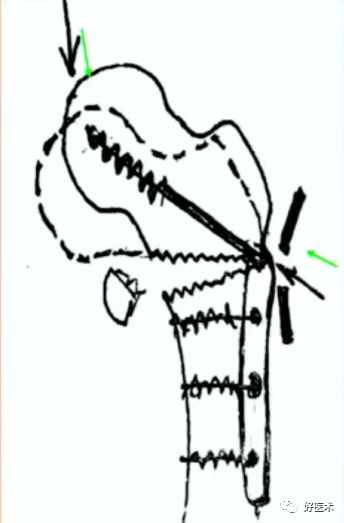

2.顶棒技术

用钉棒顶压移位骨折块来帮助复位。

病例三:女 82岁

四部分骨折,髓内钉,钢板